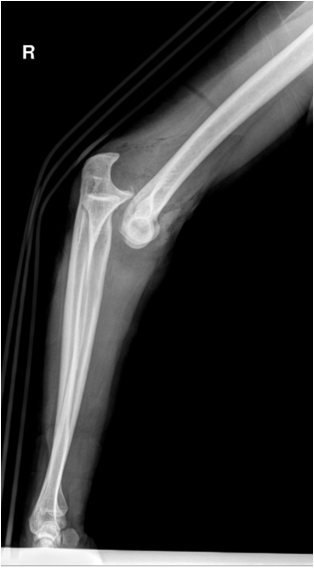

Fig. 11. Growth plate fracture with involvement of metaphysis and epiphyis (Salter-Harris type IV.